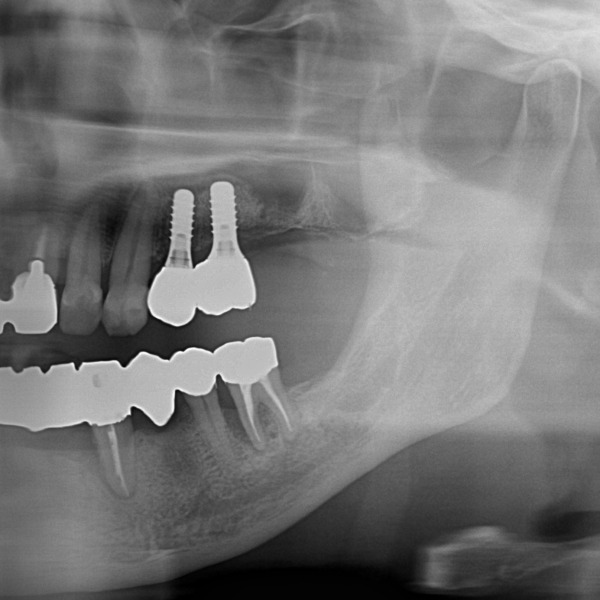

部分麻酔後、インプラントを2本同時に埋入しました。手術時間は1時間未満で、術後の腫れ・痛みもほとんどありませんでした。

インプラントと骨が結合(インテグレーション)するのを3ヶ月ほど待ち、型取りを行いました。

④被せ物のセット

被せ物が出来上がってきたので微調整を行い、口腔内にセットしました。

術後2年ほど経過していますが、インプラントは十分な骨でしっかり固定されており、問題なく何でも噛める状態です。長期間に及ぶ治療でしたが、患者様はとても満足されています。